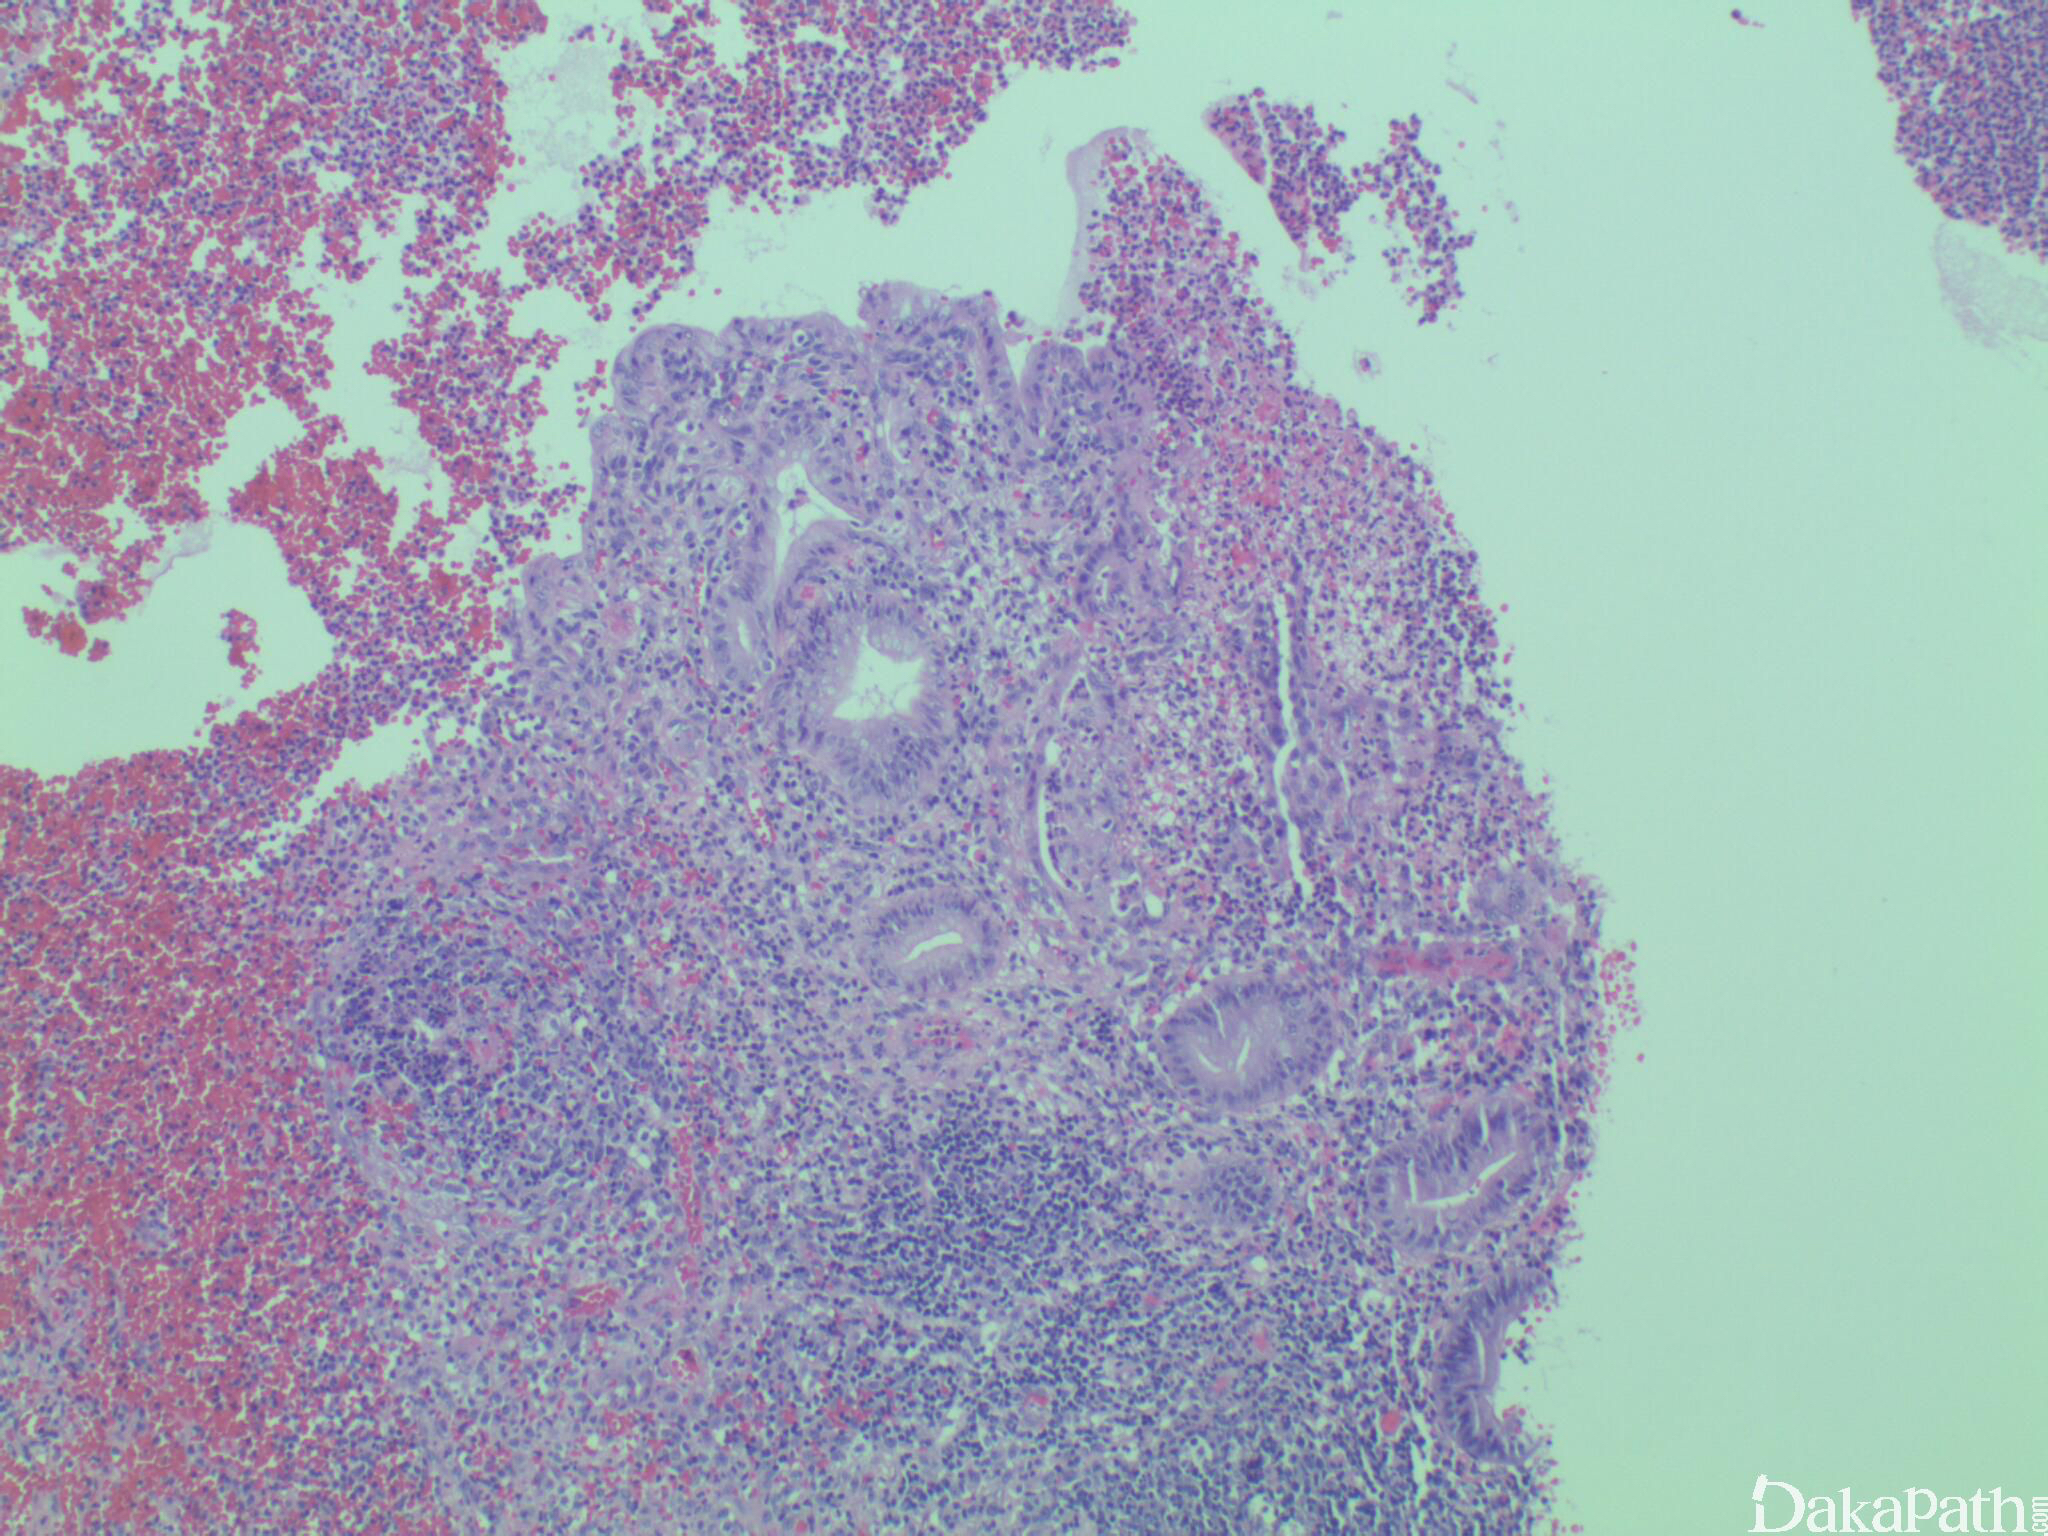

组织上阑尾壁全层或部分受累,不定量的急性炎细胞亦中性粒细胞为主,坏疽性阑尾炎可见坏死.

仅仅阑尾周围炎症表明阑尾外的原因引起。可能存在阑尾憩室,偶见高分化神经内分泌肿瘤。